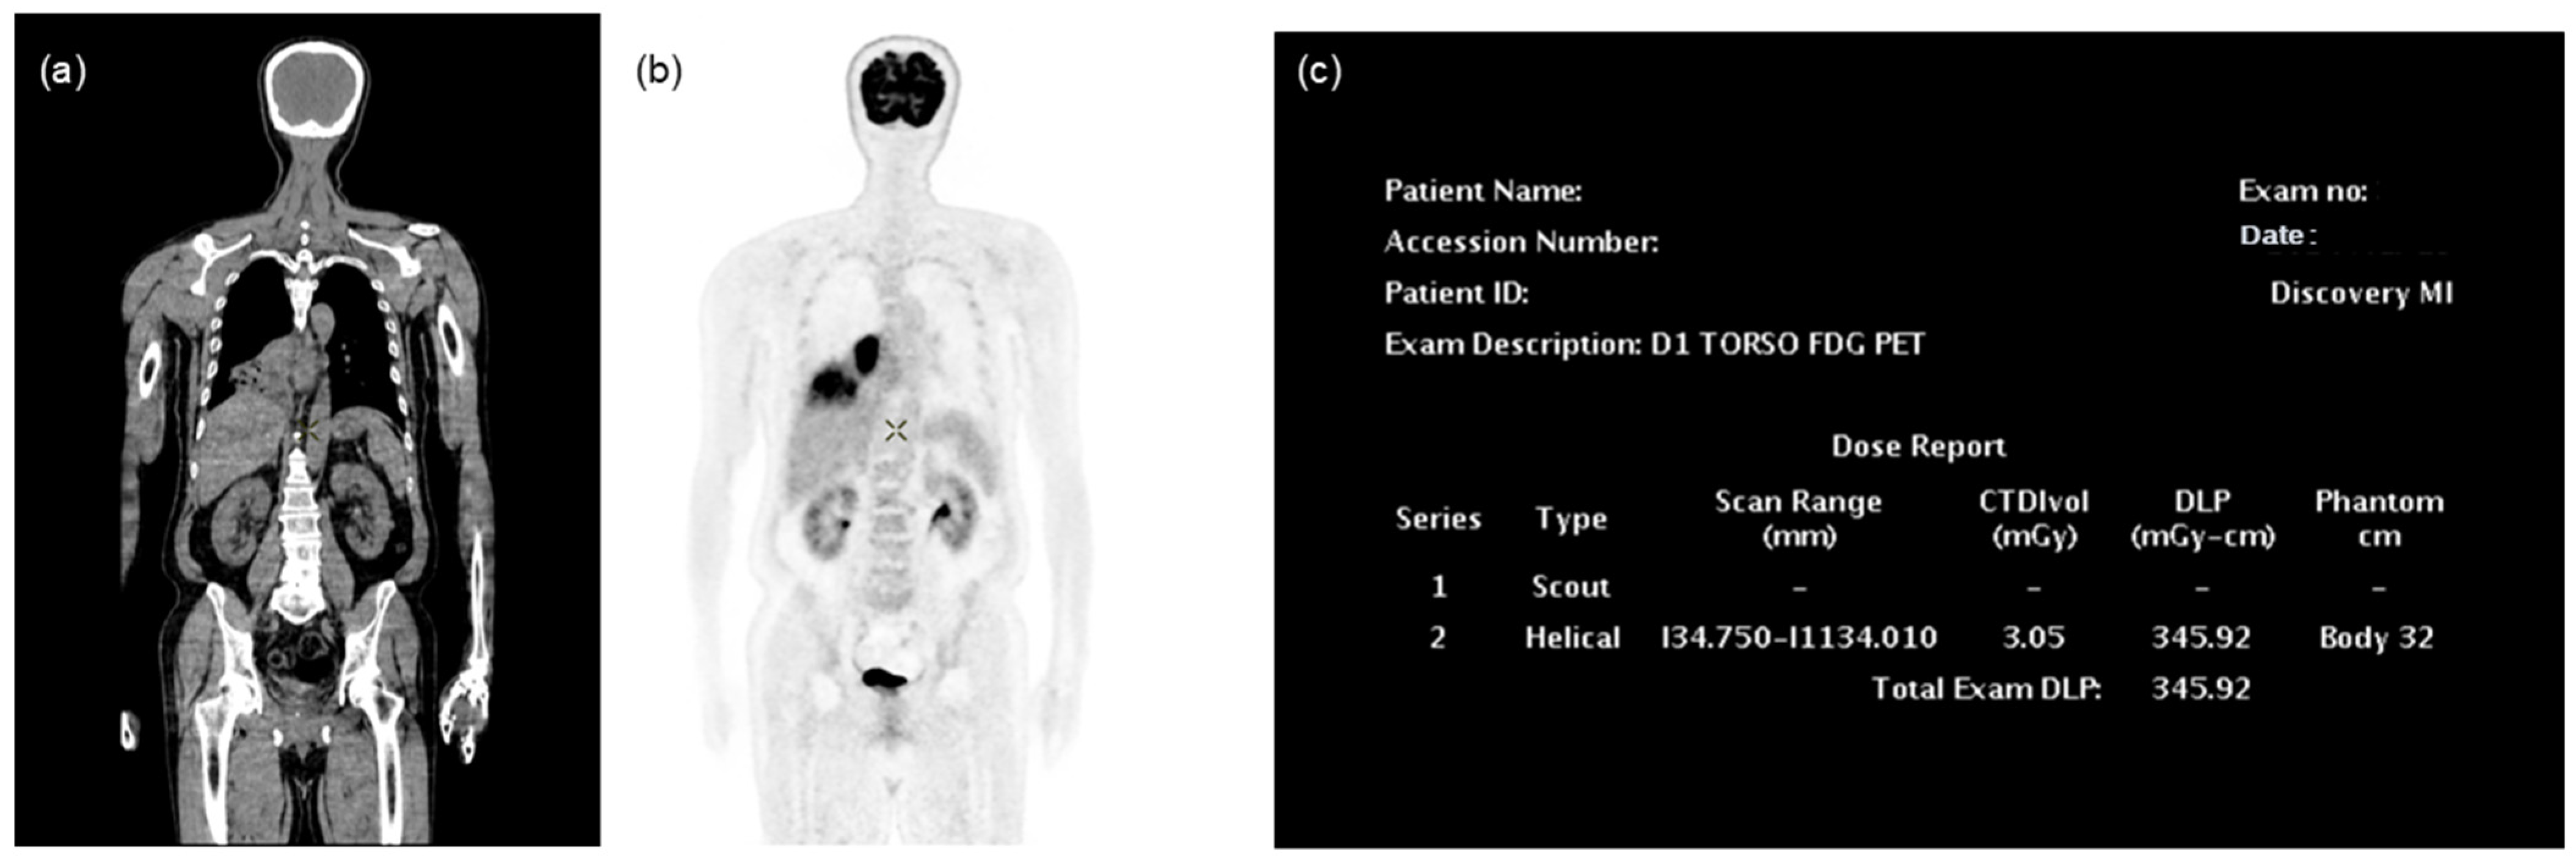

2.1. FDG PET/CT Protocol

2.2. Collection and Preprocessing of PET/CT Data

2.3. Effective Dose Calculation

2.4. Automated Effective Dose Calculation Program